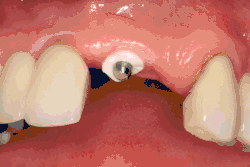

Beyond the possibility of mechanical failure[98] which may be due to poor prosthetic fitment, wear and tear, or user-induced actions such as bruxism, dental implants are also subject to peri-implant mucositis and peri-implantitis, where gum tissue and bone mass around the implant are resorbed, and the implant gradually becomes loose, and has to be removed.[99][100] In addition, although titanium is generally well tolerated by the body, there have been cases where the build-up of titanium particles released by the implant may cause systemic inflammatory response.[101] Because there is no dental enamel on an implant, it does not fail due to cavities like natural teeth. While large-scale, long-term studies are scarce, several systematic reviews estimate the long-term (five to ten years) survival of dental implants at 93–98 percent depending on their clinical use.[15][16][17] During initial development of implant retained teeth, all crowns were attached to the teeth with screws, but more recent advancements have allowed placement of crowns on the abutments with dental cement (akin to placing a crown on a tooth). This has created the potential for cement, that escapes from under the crown during cementation to get caught in the gingiva and create a peri-implantitis (see picture below). While the complication can occur, there does not appear to be any additional peri-implantitis in cement-retained crowns compared to screw-retained crowns overall.[102] In compound implants (two stage implants), between the actual implant and the superstructure (abutment) are gaps and cavities into which bacteria can penetrate from the oral cavity. Later these bacteria will return into the adjacent tissue and can cause periimplantitis.